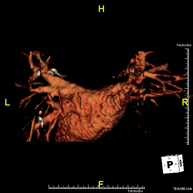

Prova diagnòstica no invasiva que consisteix en l'obtenció d'imatges d'alta definició anatòmica de les artèries caròtides i vertebrals a nivell de coll mitjançant l'ús d'un camp electromagnètic i ones de ràdio (amb un emissor i un receptor). No utilitza radiació ionitzant. En la majoria dels casos és necessari l'ús de contrast paramagnètic (Gadolini). Permet un estudi angiogràfic no invasiu gràcies a la injecció de Gadolini amb posterior reconstrucció en 2D i 3D, gràcies a estacions de treball especialitzades. Indicacions: problemes circulatoris cerebrals i síncope. - Angio-RM d'Aorta Toràcica

Prova diagnòstica no invasiva que consisteix en l'obtenció d'imatges d'alta definició anatòmica de l'aorta toràcica (principal artèria del tòrax) mitjançant l'ús d'un camp electromagnètic i ones de ràdio (amb un emissor i un receptor). No utilitza radiació ionitzant. En la majoria dels casos és necessari l'ús de contrast paramagnètic (Gadolini). Permet un estudi angiogràfic no invasiu gràcies a la injecció de Gadolini amb posterior reconstrucció en 2D i 3D, mitjançant estacions de treball especialitzades. També inclou l'estudi de la vàlvula aòrtica, informació imprescindible en el cas que el pacient necessiti cirurgia. Aquesta prova està especialment indicada en pacients que requereixen tractament quirúrgic (com a mapa vascular prequirúrgic), en el seguiment de pacients amb aneurismes d'aorta, etc. - Angio-RM d'Aorta Abdominal